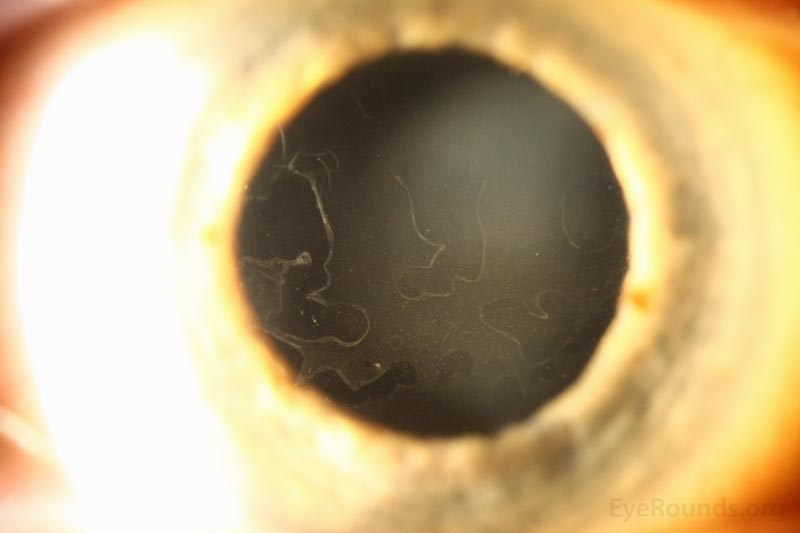

Map-dot-fingerprint dystrophy (MDFD) is a uncommon, inherited corneal dystrophy characterised by its distinctive medical look. The title itself hints on the distinctive sample of opacities that develop on the cornea, resembling a geographical map, scattered dots, and fingerprint-like whorls. Whereas seemingly a purely beauty concern, MDFD can considerably affect imaginative and prescient, resulting in lowered visible acuity, photophobia (gentle sensitivity), and even corneal blindness in extreme circumstances. This text offers a complete overview of MDFD, protecting its etiology, medical presentation, analysis, administration, and ongoing analysis.

The "map" refers back to the geographical distribution of opacities, usually involving branching and interconnected traces resembling a topographical map. The "dots" are small, discrete opacities scattered all through the cornea. The "fingerprint" sample consists of whorled or concentric traces, paying homage to fingerprints. These patterns will not be at all times current in each particular person, and their prominence can fluctuate.